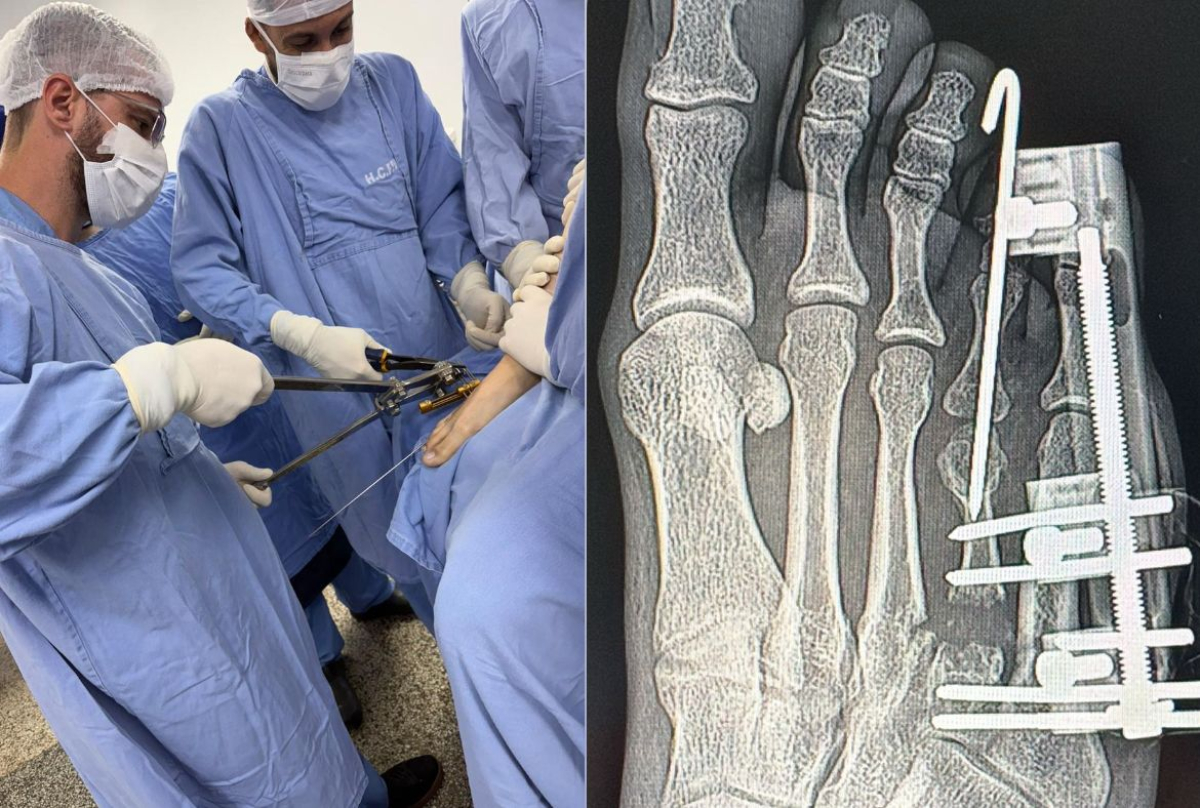

O Hospital Carlos Fernando Malzoni (HCFM) registrou um marco inédito em sua história recente ao realizar, no final de dezembro de 2025, uma cirurgia de braquimetatarsia, procedimento raro e de alta complexidade dentro da ortopedia especializada em pé e tornozelo, executado por meio de técnica percutânea, considerada menos invasiva em relação aos métodos tradicionais.

A cirurgia foi conduzida pelo ortopedista Dr. Lucas Alcaide Thomaz, profissional com experiência prévia nesse tipo de correção, e contou com o apoio de equipe anestésica especializada e a presença de diversos médicos ortopedistas, que acompanharam o procedimento de forma técnica e observacional.

A braquimetatarsia é uma malformação congênita caracterizada pelo encurtamento anormal de um dos ossos do antepé, geralmente o quarto metatarso, condição que pode causar dor, alterações na marcha, dificuldade no uso de calçados e impacto estético significativo.

O que torna o caso ainda mais singular é a forma como a cirurgia teve início, como explica o Dr. Lucas: “Durante uma aula para a turma dos alunos do 6º ano da Faculdade, a Letícia me mostrou o seu pé com um quadro de braquimetatarsia, e me perguntou se eu saberia tratar. Me relatou que já havia visitado diversos ortopedistas, sendo que nenhum tinha experiência prévia com tal tipo de cirurgia para correção do quadro. Respondi a ela que a Braquimetatarsia é extremamente rara, porém eu já havia realizada tal correção previamente, e que poderíamos resolver o seu caso. Imediatamente solicitei as radiografias no ambulatório do hospital e já iniciamos a nossa programação cirúrgica, com todo o apoio do HCFM”.

Letícia destaca que o processo ainda está em andamento, uma vez que o tratamento envolve o alongamento ósseo gradual, etapa que exige acompanhamento rigoroso. “Ainda estou na fase de alongamento ósseo, que é um processo lento e que exige paciência. Mas cada evolução representa uma melhora significativa, tanto do ponto de vista funcional quanto estético”, afirma.

De acordo com o Dr. Lucas Alcaide, “por ser uma cirurgia rara e extremamente complexa, toda a equipe dos residentes, alunos e outros colegas ortopedistas acompanharam o procedimento. Documentamos todo caso clínico e procedimento cirúrgico realizado, e iremos publicar um ‘Relato de Caso’ assim que concluirmos o desfecho da paciente”.